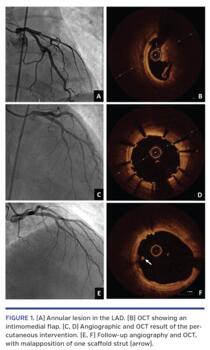

A 53-year-old man suffered a high-impact car collision. An increase in troponin levels was detected after 8 hours, so the patient underwent coronary angiography, which demonstrated an annular lesion in the proximal left anterior descending (LAD) artery (Figure 1A). Optical coherence tomography (OCT) showed an intimomedial flap and a double-lumen from the proximal to the mid LAD without significant atherosclerosis (Figure 1B). A 3.5 x 15 mm Magmaris direct magnesium resorbable scaffold (Biotronik) was deployed under OCT guidance. Then, progression of the hematoma to the mid LAD was observed, which precluded balloon postdilation and forced the implantation of a 2.5 x 15 mm Orsiro drug-eluting stent (Biotronik) in the mid LAD, achieving good final angiographic and OCT results (Figures 1C and 1D). After 3 months, OCT showed incomplete endothelialization of the bioresorbable scaffold and malapposition of one strut at its proximal edge, possibly due to positive vessel remodeling (Figures 1E and 1F). Conservative management with prolonged dual-antiplatelet therapy was decided.

The treatment of coronary lesions caused by blunt chest trauma is controversial. As far as we know, this is the first report of a coronary dissection related to blunt chest trauma evaluated with OCT and treated with a magnesium resorbable scaffold. OCT verified that the dissection took place on a previously healthy artery. In addition, follow-up OCT allows the evaluation of vessel remodeling as well as the diagnosis of alterations in the scaffold, such as malapposition, which can determine changes in the patient’s treatment.